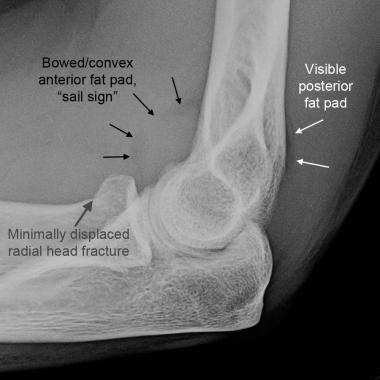

What might you see on x-ray of someone with a radial head fracture?

Sail sign (elevation of anterior fat pad)